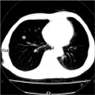

最新のマルチスライスCTでより安全な精密検査が受けられます。

当院では、最新のマルチスライスCTスキャナを設置しております。

この検査では、患者様が寝台に横になるだけで、苦痛なく胸部や腹部の断層像(輪切り)が鮮明に撮れます。

とくに、16スライス連続してデータを収集することができ従来の装置より広範囲の検査が行え、胸部疾患および腹部臓器(肝・胆・膵・腎膀胱・その他)疾患にいたるまで、全身の診断が可能です。

■胸部肺がん